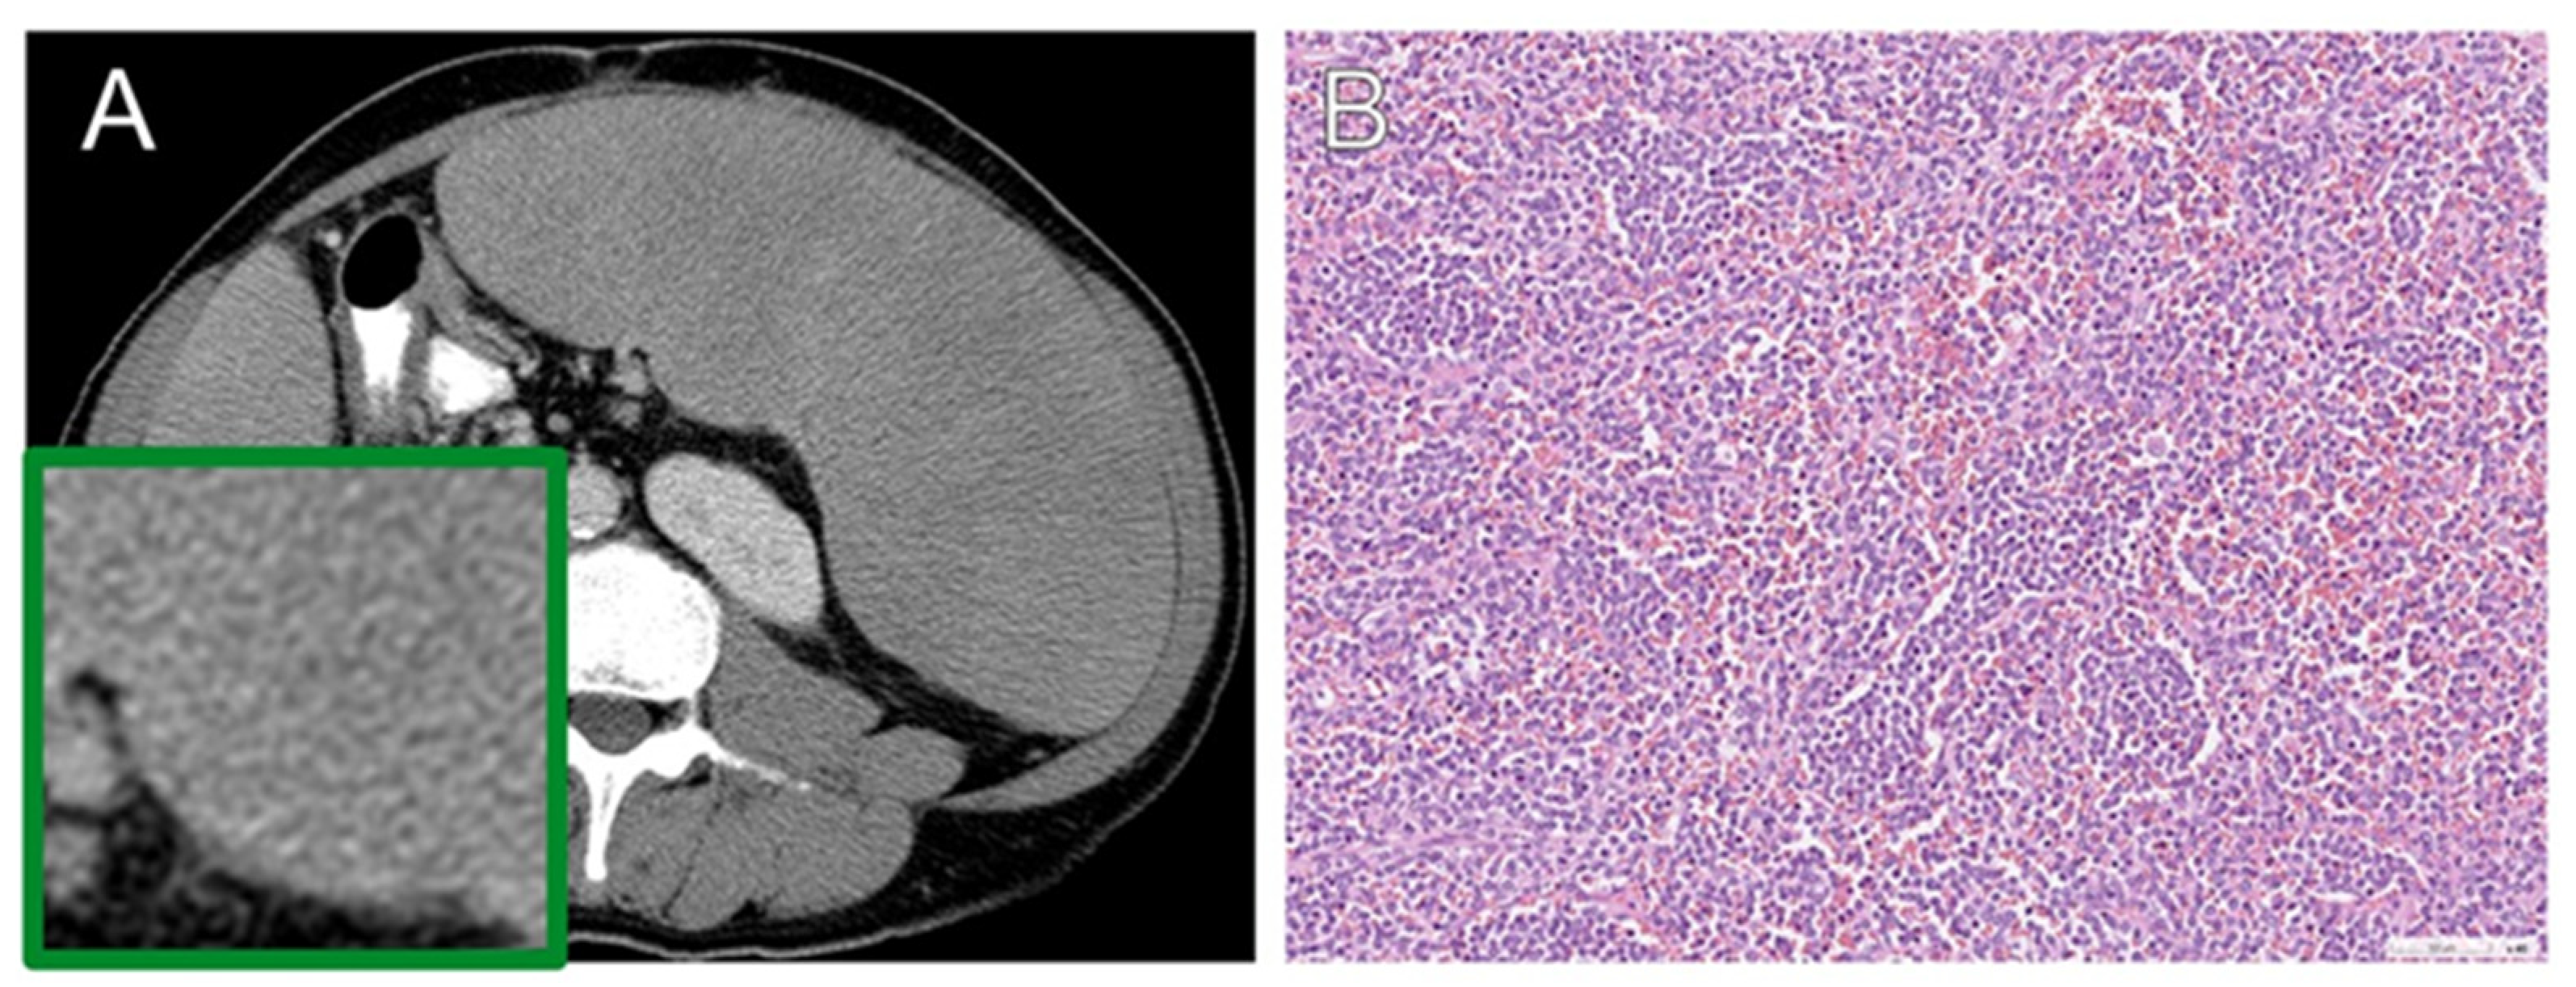

3.5. Histopathology